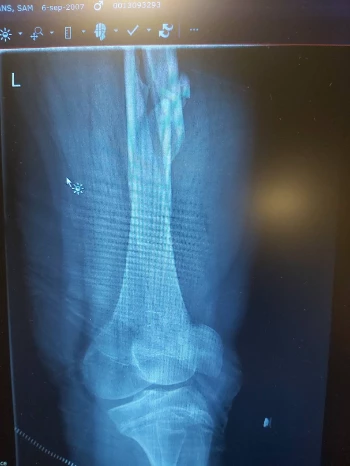

Elleboog: 2 operaties, Openpolsbreuk ook 2 operaties, scheenbeen, kuitbeen, groeischijf + 3x knieschijf knie is geopereerd, dijbeen op 3 plaatsen gebroken, rug ineengezak voor 32%

Nu zit er een ijzerenstaaf van zijn heup tot zijn knie om zijn dijbeen meer steun te geven is te zwak, 15 bouten en 3 ijzerplaten in zijn.enkeltje en een ijzerendraad met 2 bouten rond zijn knieschijf om deze op zijn plaats te houden want door de breuken zat zijn knieschijf 5cm boven waar ze normaal moet zitten. De chirurg heeft ons verwittigd dat als hij nog 1x zijn knie breekt dat ze er dan niets meer aan kunnen doen en zijn been dan zou verliezen. Zijn 1 been is 1cm korter dan het ander waardoor zijn rug en heup scheef begint te groeien. En dit geeft veel pijn en ontstekingen aan zijn rug en heup.

We proberen ook deze zeldzame ziekte meer onder de mensen te krijgen want er zijn maar weinig mensen die deze ziekte kennen. Er zijn zelfs dokters die de ziekte niet kennen zo zeldzaam is het. Het is soms zo erg dat ouders worden beschuldigd van het mishandelen van hun kinderen omdat ze zoveel breuken oplopen. Mijn zoon doet ook mee met een experimenteel onderzoek in Leuven met een nieuw medicijn dat de botten sterker zou moeten maken. Hopelijk gaat dit werken. 10 breuken en 16 operaties is meer dan genoeg geweest en er komt nog 1 operatie voor zijn enkel aan.